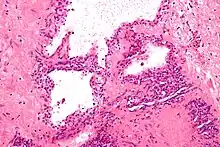

Micrograph showing a pancreatic serous cystadenoma, a type of cystadenoma. H&E stain. | |